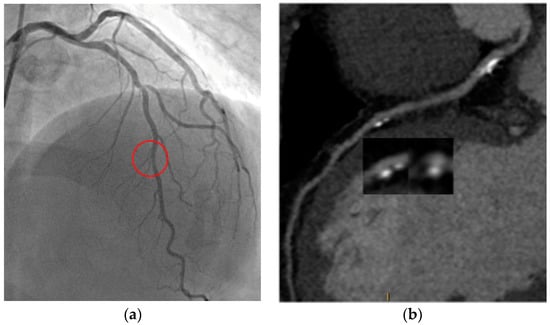

6.2. Stress CTP

- Rossi, A.; Merkus, D.; Klotz, E.; Mollet, N.; de Feyter, P.J.; Krestin, G.P. Stress myocardial perfusion: Imaging with multidetector CT. Radiology 2014, 270, 25–46. [Google Scholar] [CrossRef] [PubMed]

- Pontone, G.; Andreini, D.; Baggiano, A.; Bertella, E.; Mushtaq, S.; Conte, E.; Beltrama, V.; Guaricci, A.I.; Pepi, M. Functional relevance of coronary artery disease by cardiac magnetic resonance and cardiac computed tomography: Myocardial perfusion and fractional flow reserve. BioMed Res. Int. 2015, 2015, 297696. [Google Scholar] [CrossRef] [PubMed]

- Pontone, G.; Baggiano, A.; Andreini, D.; Guaricci, A.I.; Guglielmo, M.; Muscogiuri, G.; Fusini, L.; Soldi, M.; Del Torto, A.; Mushtaq, S.; et al. Diagnostic accuracy of simultaneous evaluation of coronary arteries and myocardial perfusion with single stress cardiac computed tomography acquisition compared to invasive coronary angiography plus invasive fractional flow reserve. Int. J. Cardiol. 2018, 273, 263–268. [Google Scholar] [CrossRef] [PubMed]

- Mehra, V.C.; Valdiviezo, C.; Arbab-Zadeh, A.; Ko, B.S.; Seneviratne, S.K.; Cerci, R.; Lima, J.A.; George, R.T. A stepwise approach to the visual interpretation of CT-based myocardial perfusion. J. Cardiovasc. Comput. Tomogr. 2011, 5, 357–369. [Google Scholar] [CrossRef]